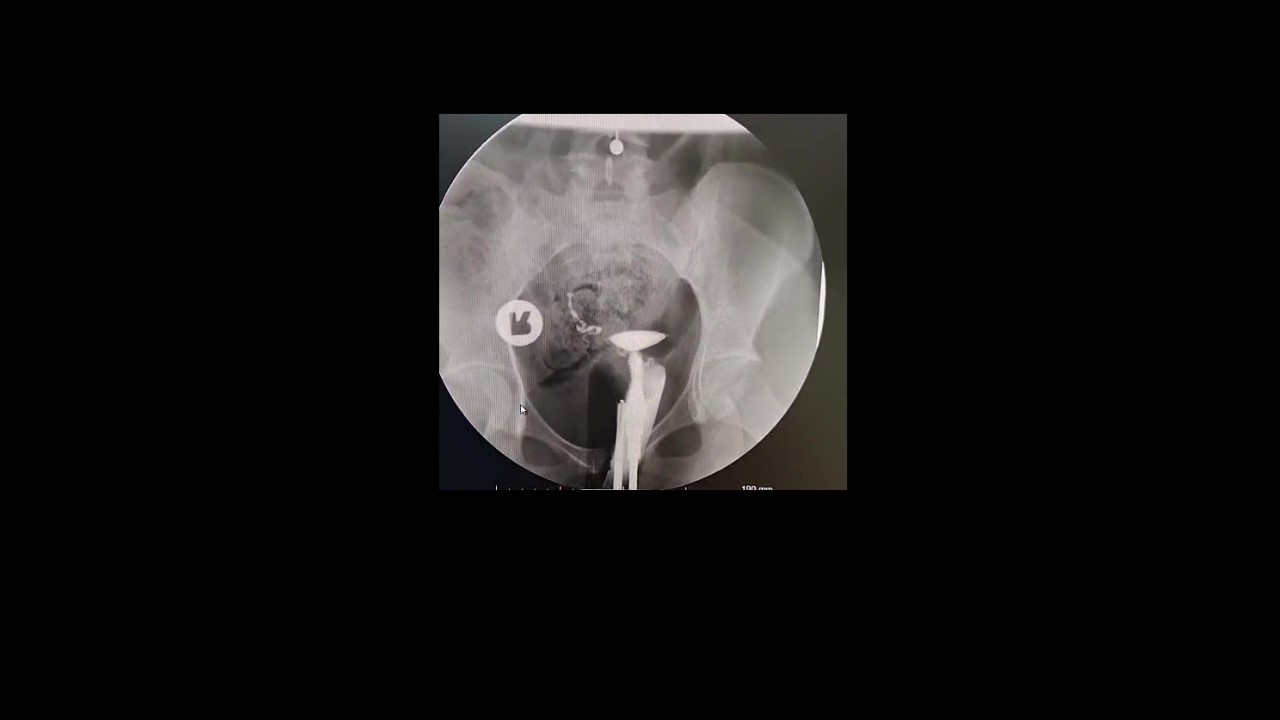

Histerosalpingografi (HSG), rahim ve tüplerin detaylı olarak değerlendirilmesini sağlayan önemli bir görüntüleme yöntemidir. Özellikle çocuk sahibi olmak isteyen kadınlarda tüplerin açık olup olmadığını anlamak için sıklıkla tercih edilir.

Rahim iç yapısının değerlendirilmesi, tüplerin açıklığı, kontrast geçişinin özellikleri ve olası patolojilerin doğru şekilde tanımlanması; tedavi planını doğrudan etkiler. Eksik veya yüzeysel raporlar, yanlış yönlendirmelere ve zaman kaybına neden olabilir.